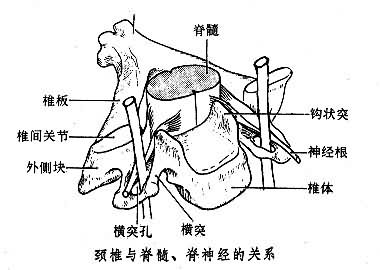

脊髓损伤多见于青壮年,男性多于女性,每年的发病率约为20~60/100万人,常导致肢体运动障碍,多伴发与脊…「 阅读全文 」